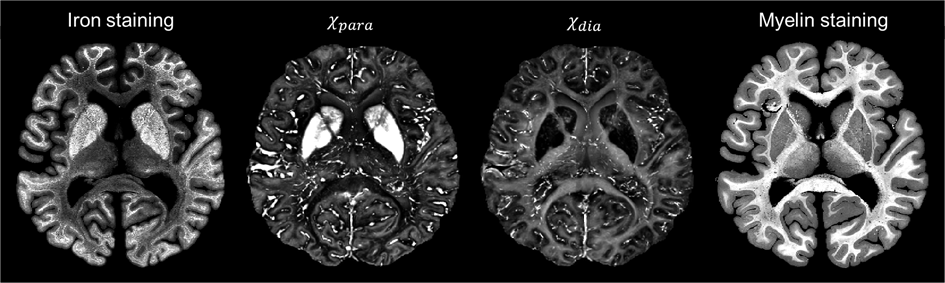

χ-separation is an advanced Magnetic Resonance Imaging (MRI) technique that generates maps of paramagnetic and diamagnetic tissues, potentially reflecting the distribution of the paramagnetic iron and diamagnetic myelin in the brain. This method has been applied in various studies of neurological diseases such as multiple sclerosis, Parkinson’s disease, and multiple system atrophy.

The results showed statistically significant linear correlations between paramagnetic susceptibility values and iron staining optical density, as well as between diamagnetic susceptibility values and myelin staining optical density. Qualitative comparison revealed clearly delineated substructures in several brain regions such as the laminar structures of the globus pallidus and the subthalamic nuclei, within both the paramagnetic and diamagnetic susceptibility maps regions. However, some areas of high myelin concentration within the globus pallidus in the basal ganglia were not well represented in the diamagnetic susceptibility map. This discrepancy may highlight the need for further improvements in the χ-separation.